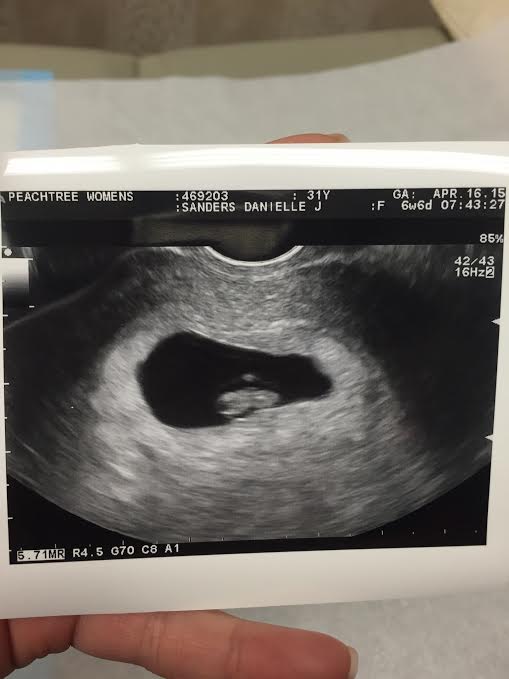

But – there is a baby. There is fetal movement. There is a heartbeat. A strong heartbeat.

Everything looks perfect right now. The growth is perfect. The heartbeat is 141. My OBGYN says we are at a less than 5% chance of another loss. (This site also brings me comfort – as of today I’m at 2.6% and this site.) My progesterone has risen so much (15.4 to 41.4) they’ve cut my supplements back to only once a day instead of twice a day. They said the brown spotting was old blood and it’s my body clearing everything out to make room. They aren’t scared. They aren’t worried. They keep telling me I shouldn’t be either. Easier said then done, though given our history.

My OBGYN is fantastic. My NP is an angel. The whole office makes you feel like family. They know me by name since I was there so often with fertility treatments. My OB is good to me and knows how petrified I am, so he ordered my next ultrasound for two weeks instead of the standard four weeks. Which means we get to see Lil Baby Fat(titude) next Thursday (4/30).

So, fingers crossed. It’s still early, but developmentally – we’ve never made it this far. The first time all growth stopped at 6w0d (despite not finding we’d had a missed miscarriage until 10w3d) and it was rocky from day one and the second time I started miscarrying naturally at 5 weeks. And today, today I am 7w5d with movement and confirmed development at 6w6d…and everything looks perfect. My OBGYN uses the word “healthy.” Everything is “healthy” for the first time ever.